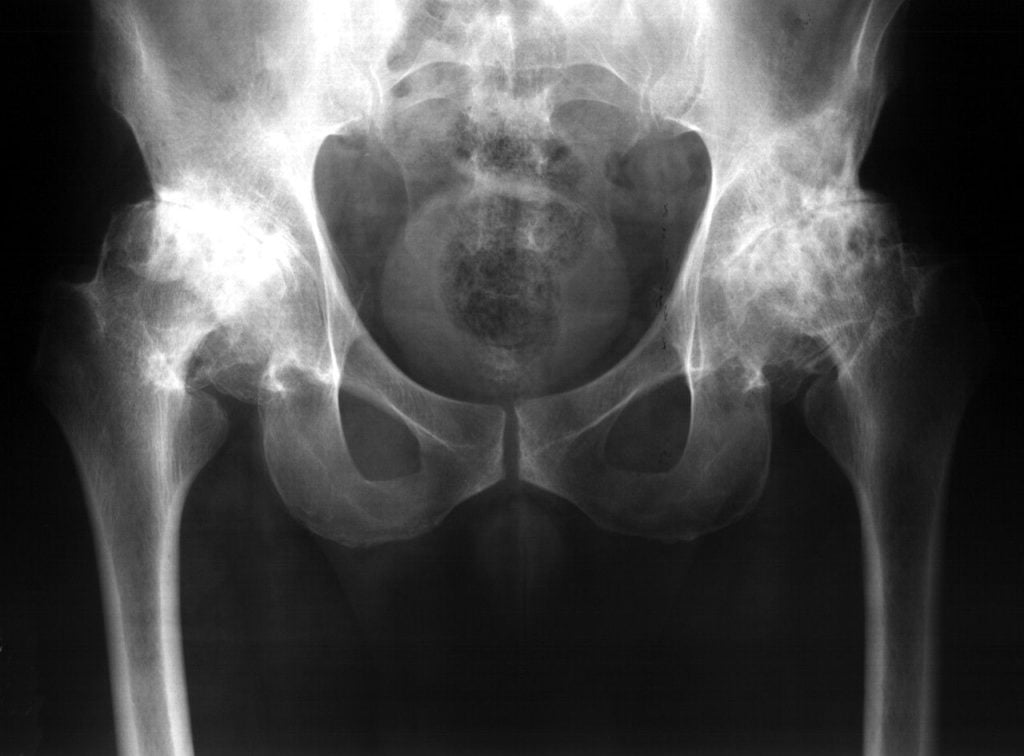

Двухсторонний коксартроз 1-2 степени: диагностика и лечение

Односторонний или двухсторонний коксартроз 1, 2 степени – это симптоматические разновидности дегенеративно-дистрофического нарушения в тазобедренном сочленении, обусловленные прогрессирующим разрушением суставного хряща, при котором соединительные ткани утрачивают свою морфологическую целостность.

Особенности различных степеней поражения остеоартрозом (коксартрозом) тазобедренного сустава (ТБС) будут рассмотрены в данном материале.

Остеоартроз (коксартроз) ТБС